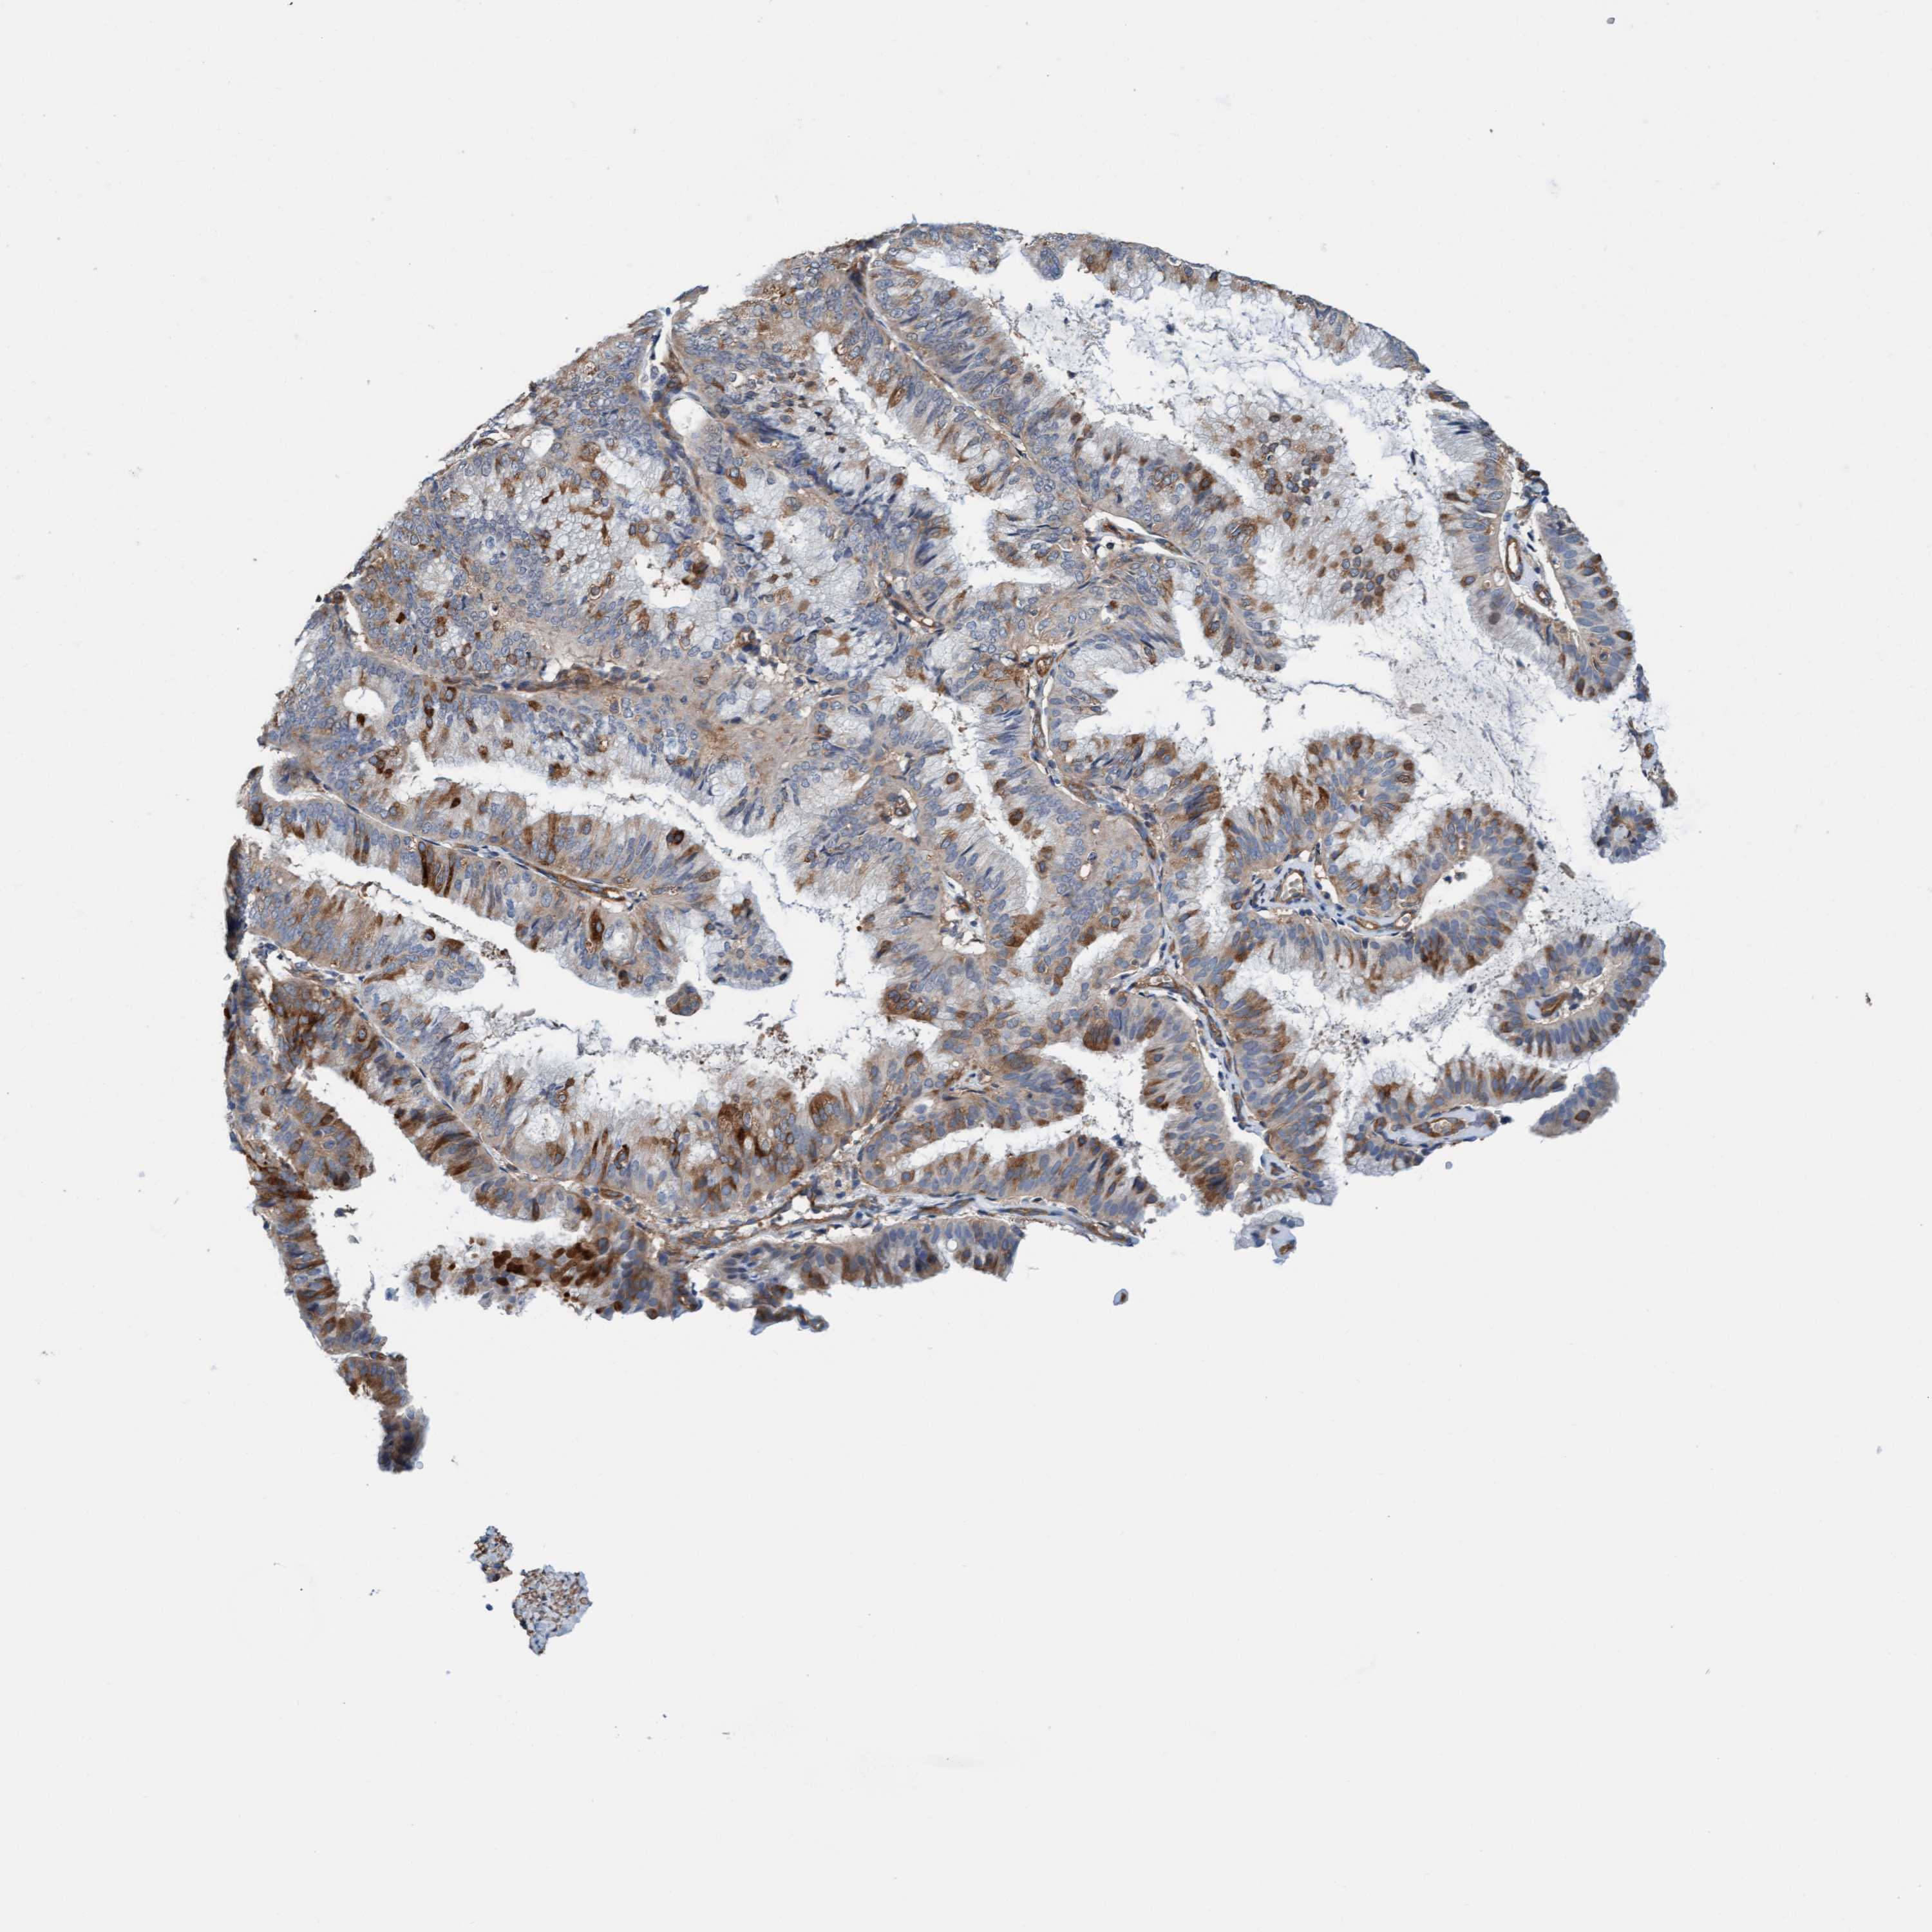

ENDOMETRIAL CANCER - Protein expressioni

A mouse-over function shows sample information and annotation data. Click on an image to view it in a full screen mode. Samples can be filtered based on level of antibody staining by selecting one or several of the following categories: high, medium, low and not detected. The assay and annotation is described here.

Note that samples used for immunohistochemistry by the Human Protein Atlas do not correspond to samples in the TCGA dataset.

Antibody stainingi

Antibody staining in the annotated cell types in the current human tissue is reported as not detected, low, medium, or high, based on conventional immunohistochemistry profiling in selected tissues. This score is based on the combination of the staining intensity and fraction of stained cells.

Each image is clickable and will lead to virtual microscopy that enables deeper exploration of all samples and also displays staining intensity scores, fraction scores and subcellular localization as well as patient and tissue information for each sample.

Antibody HPA002552

Antibody HPA023201

Staining

High

Medium

Low

Not detected

Intensity

Strong

Moderate

Weak

Negative

Quantity

>75%

75%-25%

<25%

None

Location

Nuclear

Cytoplasmic/membranous

Cytoplasmic/membranous,nuclear

Adenocarcinoma, NOS

Adenoma, NOS